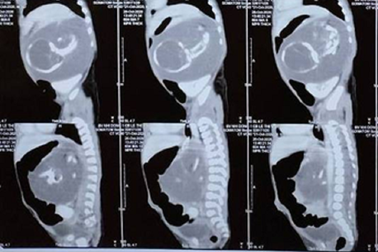

Bé trai chào đời mang theo người em song sinh… trong bụngChào đời với khối u có kích thước lớn trong bụng, bác sĩ xác định đó chính là người em song sinh của bệnh nhi. Cuộc phẫu thuật thành công đã trả lại cho bé cơ thể bình thường.